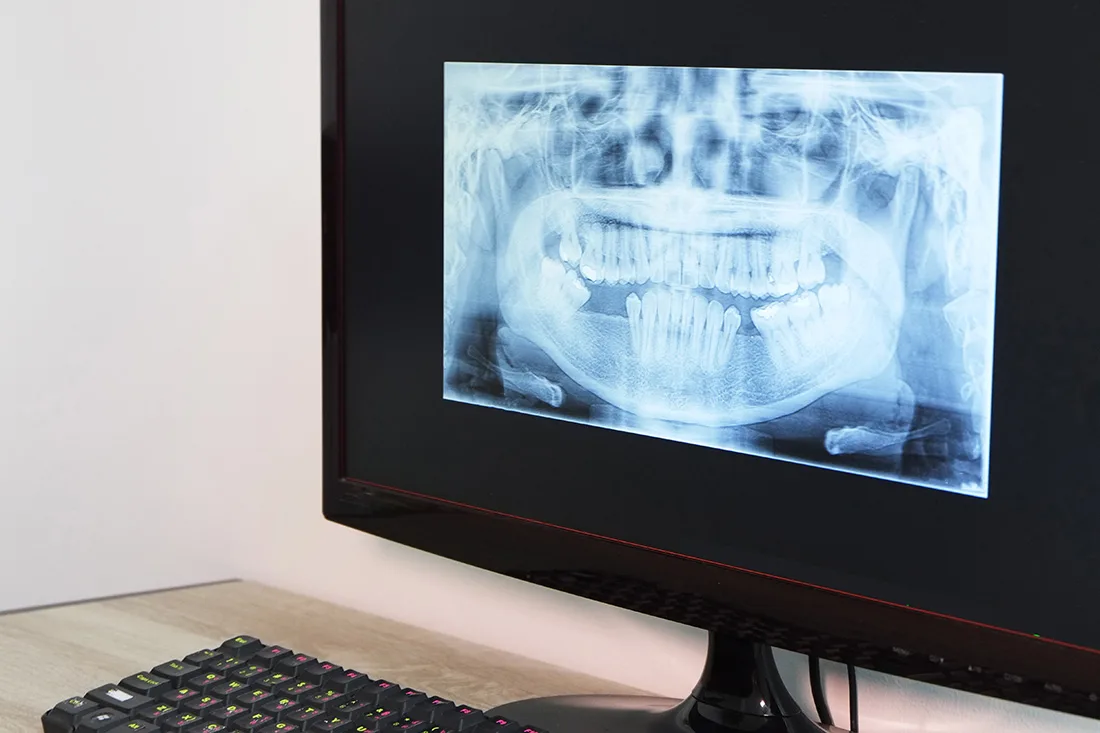

Digital X-Rays

Digital x-rays are safe, quick, and comfortable. Using the latest technology, we can create crisp, high-resolution images of your mouth’s structure, so we can make accurate diagnoses and treatment plans. Digital x-rays use only a fraction of the radiation as traditional film x-rays, so you can rest easy. Most patients receive one full set of x-rays every year, but we may recommend additional imaging in the case of a dental emergency, or if we find an oral health issue that we need to investigate further.